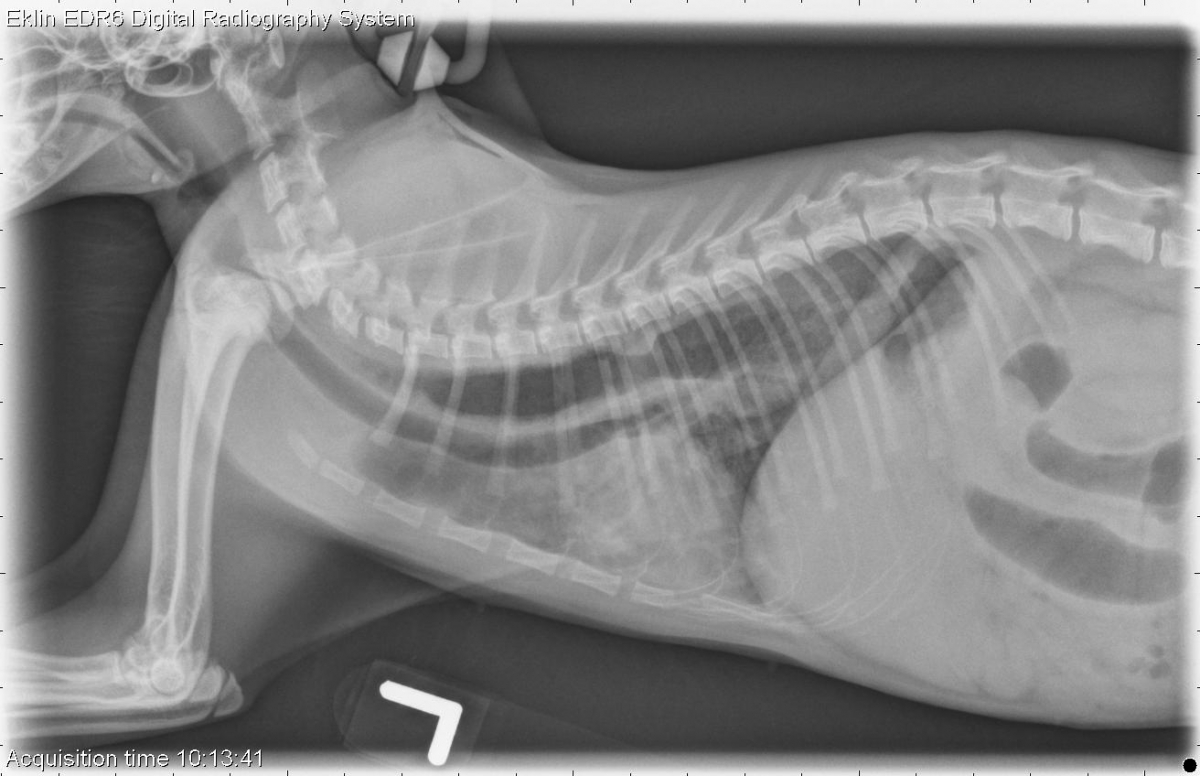

Today’s case is a 5 month old domestic long haired cat with regurgitation. Take a look and post your interpretation in the comments!

R LAT Thorax

There is diffuse severe gas distention of the esophagus within the thorax. The mucosal surfaces of the esophagus appears irregular. On the lateral projections, there is a focal soft tissue density contiguous with the dorsal wall of the esopahgus at the level of the 6th thoracic vertebrae. There is diffuse interstitial to alveolar infiltrates within the ventral lungs bilaterally. The liver is mildly enlarged.

Megaesophagus – most likely idiopathic/congenital. No evidence of vascular ring anomaly.

Megaesophagus and aspiration pneumonia